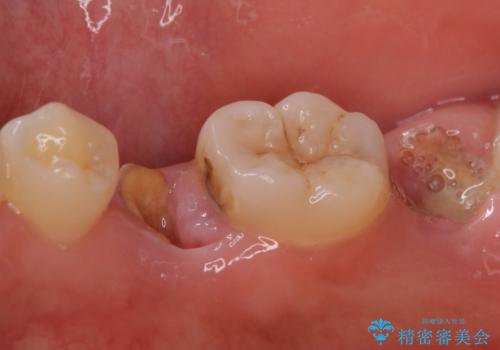

- 歯が折れてなくなってしまったことを主訴に来院された患者様です。

精査したところ、右下の奥歯2本(右下75)は大きなう蝕により歯冠が崩壊し保存不可能な状態でした。

保存不可能な歯を抜去し、オールセラミックのブリッジによる補綴治療を行いました。